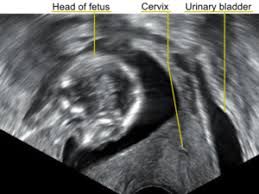

Female pelvis ultrasound sonography plays the primary role in imaging of the female pelvis. Primary indications for female pelvic us examination are pelvic pain, abnormal vaginal bleeding, and suspicion of pelvic mass. An ultrasound of the female pelvis may be performed by examination of the abdomen, called transabdominal, or by using a special probe designed to be inserted into the vagina, called transvaginal. Ultrasound imaging uses soundwaves to create pictures of the inside of the body. However, it is considered more invasive than the transabdominal approach. • normal and ectopic pregnancy implantation can be accurately Within the right ovary, there is a 2.5 cm thick walled cyst with crenulated inner margin and peripheral vascularity consistent with a corpus luteum. A transabdominal (ta) evaluation and a transvaginal (tv) / endovaginal (ev) evaluation. Further charac terization of a pelvic abnormality noted on another imaging study 14. A pelvic ultrasound is a noninvasive diagnostic exam that produces images that are used to assess organs and structures within the female pelvis. Measurements should be recorded for simple/complex/dermoid cysts. Transvaginal ultrasound is a test used to look at a woman's uterus, ovaries, tubes, cervix and pelvic area. Both ovaries should be identified and measured if appropriate again in 3 planes.

Make sure to have a drape/sheet and cover the patient properly. Evaluation of excessive bleeding, pain, or signs of infection after pelvic surgery, delivery, or abortion 16. Report whether any mass is delineated. Evaluation for signs or symptoms of pelvic infection 13. A pelvic ultrasound allows quick visualization of the female pelvic organs and structures including the uterus, cervix, vagina, fallopian tubes and ovaries. No cysts are identified (a __ cm round, anechoic cyst is noted or normal follicles are identified). Both ovaries should be identified and measured if appropriate again in 3 planes. Pelvic ultrasound is usually the initial modality for imaging gynecologic pathology, including acute pelvic pain and chronic pelvic pain.

Transvaginal ultrasound is a test used to look at a woman's uterus, ovaries, tubes, cervix and pelvic area. An ultrasound of the female pelvis may be performed by examination of the abdomen, called transabdominal, or by using a special probe designed to be inserted into the vagina, called transvaginal. This gynaecological scan is available to post menopausal women (i.e. It is normal in echogenicity with normal vascular flow. Please refer to the articles on pelvic ultrasound, for a discussion about this study, and on normal genitourinary tract. 1 year after last period). Ultrasound imaging uses soundwaves to create pictures of the inside of the body. An ultrasound of the pelvis is typically used to look at the bladder, ovaries, uterus, cervix, and fallopian tubes (some of these are known as the female reproductive organs). A hand held device called a transducer (also called a probe or wand) sends and receives these soundwaves. Ultrasound of the female pelvis is important for diagnostic accuracy. The left ovary measures __ x __ x __ cm in diameter and demonstrates normal vascular flow and echogenicity. A pelvic ultrasound allows quick visualization of the female pelvic organs and structures including the uterus, cervix, vagina, fallopian tubes and ovaries. Normal bilateral ovaries without evidence of.